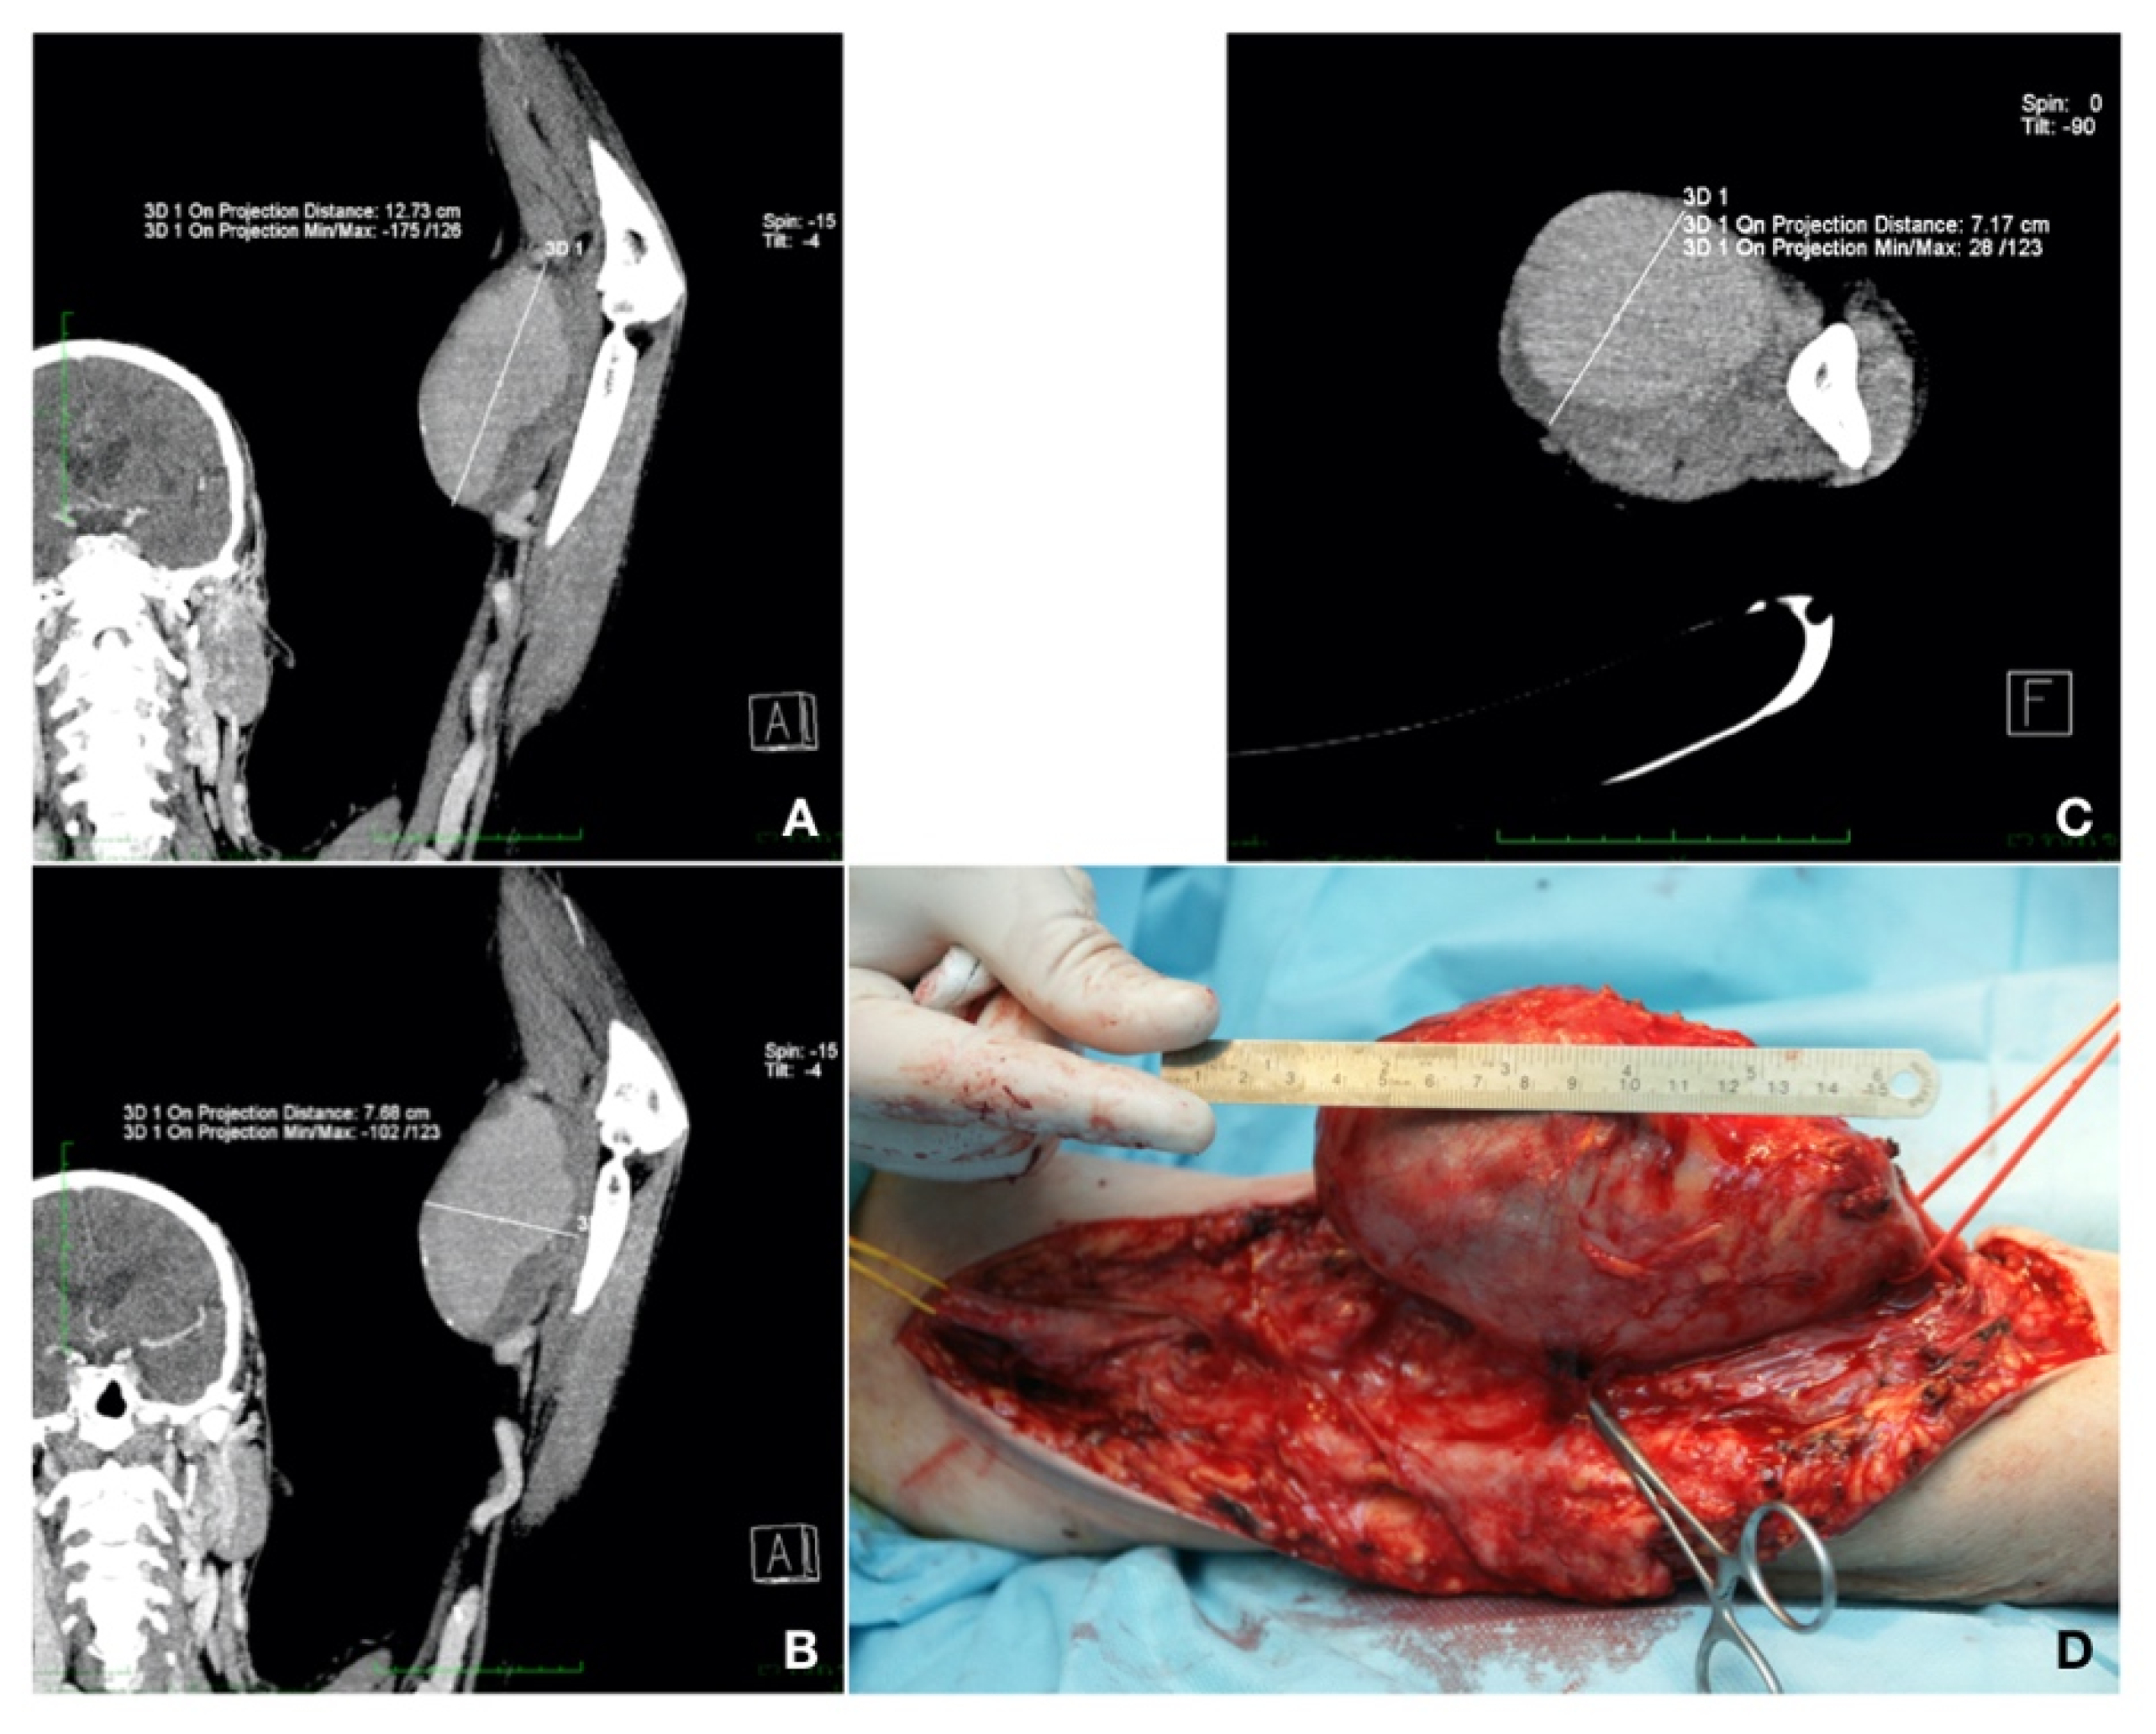

Case 1. A 59-year-old patient presented with a left brachial mass that had developed during the past 3 years. The patient also had type 2 diabetes mellitus, treated with diet, and dyslipidemia, treated with a statin. The mass was approximately 10 cm in size, pulsatile, but without any particular symptoms. The patient was known for chronic glomerulonephritis and chronic renal disease stage 5 KDIGO for 5 years. Three years previously, he had undergone live donor renal transplantation and, since then, he had been on immunosuppressive and steroid agents (fujimycin 0.5 mg, mycophenolic acid 2 × 180 mg, and prednisone 5 mg daily). After the RT, the AVF on the left side was closed. The patient was currently undergoing chronic RT rejection and hemodialysis three times per week. A CT-Angio of the left arm showed a brachial artery aneurysm of 12.73/7.68 cm, partially thrombosed. Aneurysm resection and vascular reconstruction with spatulated end-to-end anastomosis were performed [

7]. The patient received preoperatively an adjusted dose of Ceftriaxone

® (Antibiotice S.A., Iasi, Romania) at 1 g/dosage for infection prevention. An aneurysmectomy and reversed saphenous vein graft interposition, end-to-end anastomosis with 6.0 Prolene

® (BBraun, Hessen, Germany) continuous sutures were performed under general anesthesia. The postoperative evolution was without complications (embolic, neurological, or surgical site bleeding or infection) and the patient was discharged 10 days after surgery (

Figure 2).